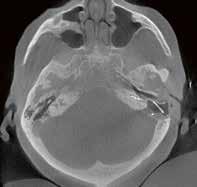

2. Vergleich eines cranialen CTs mit und ohne Deep Learning Rekonstruktion AiCE:

CTDI

30,2 mGy 544,6 mGy*cm

Felsenbein-CT Felsenbein CT-Rekonstruktion

Elektrode

CCT AIDR

der

Felsenbein-DVT

CCT AiCE

Vergleich

DVT: CDTI DLP Volumen-CT 6,5 mGy 39 mGy*cm DVT 7,3 mGy 76,6 mGy*cm Vorgänger-CT 17,1 mGy 176 mGy*cm CT vs. DVT

„AiCE unterstützt die Diagnosefindung in der Neuroradiologie dank der sofort sichtbar besseren Bildqualität bei gleicher Dosis.“

1.

einer Felsenbeinaufnahme, CT vs.

VISIONS 31 // 19 © 2021 C ANON MEDICAL SYSTEM S

DLP

Dosis